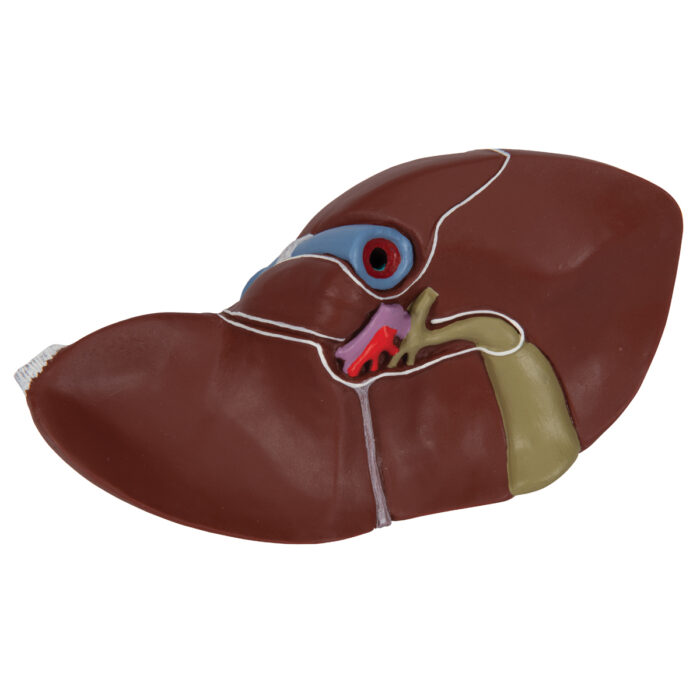

This realistic model shows the anatomy of the liver and gall bladder. The Liver with gall bladder shows:

4 lobes with gall bladder

Extrahepatic ducts

Hilus vessels

- Shows: 4 lobes with gall bladder, Extrahepatic ducts, Hilus vessels

Liver and Gall bladder properties featured:

- Liver

- Right lobe of liver

- Left lobe of liver

- Quadrate lobe

- Caudate lobe

- Proper hepatic artery

- Hepatic portal vein

- Common hepatic duct

- Neck of gallbladder

- Gallbladder